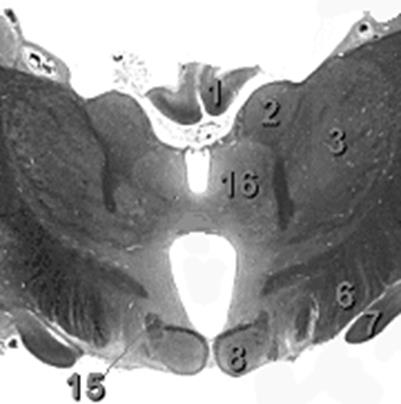

Рис. 4. Поперечный срез мозга на уровне сосцевидных тел.

1. Fornix

2. Nucleus anterior thalami

3. Nucleus lateralis posterior thalami

6. Pedunculus cerebri

7. Tractus opticus

8. Corpus mammillare

15. Fasciculus mammillaris princeps

16. Nucleus dorsomedialis thalami